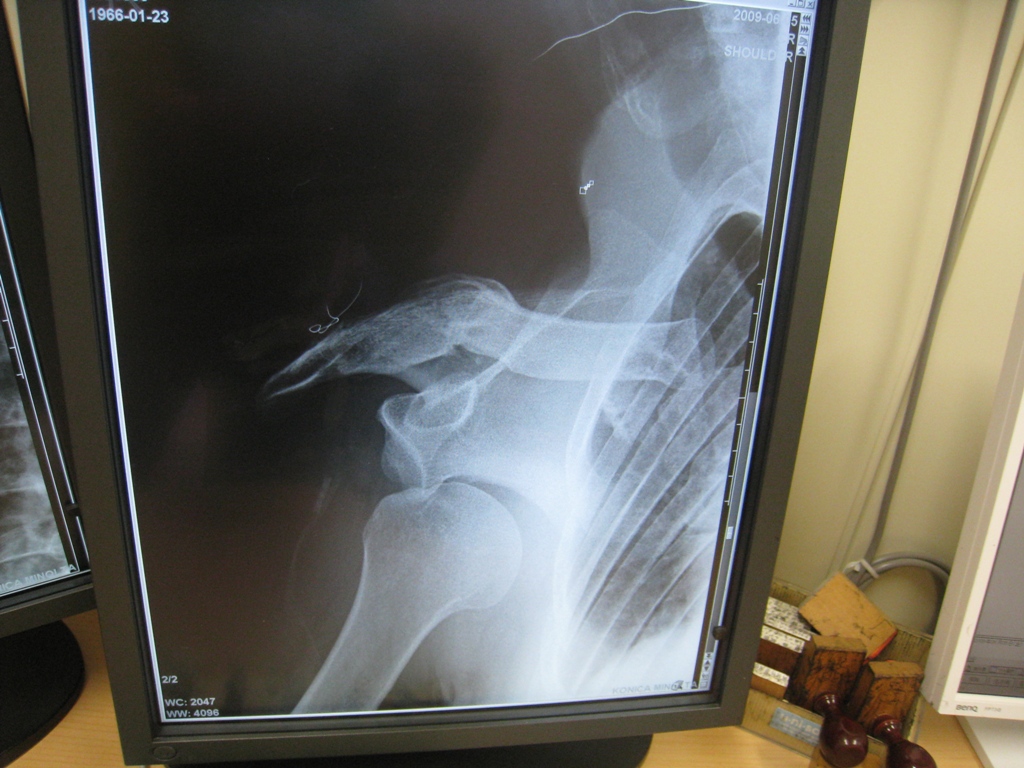

トレーニング中にヒョンなアクシデントから右肩を外傷性肩関節脱臼・靭帯損傷・・

お陰で短い時間で直ぐ検査をして、元通りにはめてもらったが、はめ込んでる時の更なる激痛は酷かった! それもはめ込むまで1時間以上もかかってやっとのことだったから始末が悪い。

損傷した肩は脱臼がクセや今後手術にならないように数週間は右腕固定・・・なんだって。

関節唇という軟骨を損傷しているため、しっかり固定しても再脱臼の危険性は高くなるらしく、関節唇ってのは二度と再生もしない。

まっ、今更再生しない人体部分を取り上げたらキリが無いし(笑)然程問題はないけど、 再発は勘弁!

数週間のギブス、、、 大事をとって今は固定しているけれども。

(写真左が脱臼しているレントゲン画像で、写真右が元に戻した後の画像)

左の写真は肩が下がり、残った部分はまるで、プロテクターのようになっていた。

骨を折る場所にもよるが、鎖骨折るよりは、はるか~に痛かった!